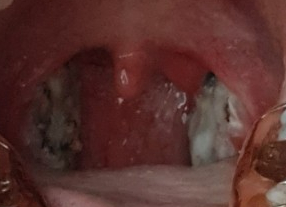

싫어서 작게 올립니다!하얀 골짜기가 끼어서 불에 탄 부분이 가끔 보입니다.비포랑 비교해보니 목이 많이 넓어졌어요.근데 생각보다 많이 제거된 것 같지 않은 느낌이었어요. ㅎㅎㅎ

다음날부터 계속 사진 괴롭히기 주의

보시면 아시겠지만, 경사가 떨어지고 나서 없어진 편도선이 눈에 띄기 시작합니다.하도 밥을 잘 먹어서 경사는 언제 떨어졌는지 모르게 떨어졌어요.